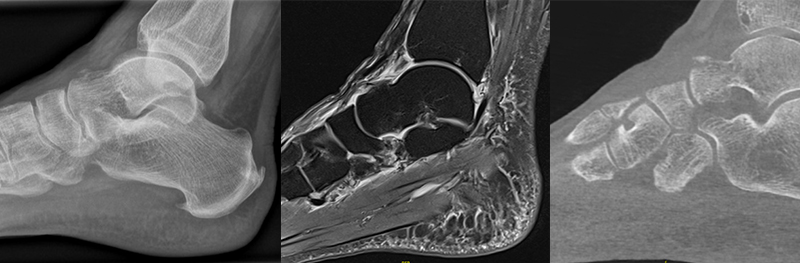

Bei Distorsionen des Sprunggelenks/Fußes stellen konventionelle Röntgenaufnahmen die initiale Standarddiagnostik dar 2021. In Abhängigkeit der Beschwerdelokalisation sollten Röntgenaufnahmen des Sprunggelenks in zwei Ebenen bzw. des Fußes in drei Ebenen angefertigt werden. Frakturen des Processus anterior werden aufgrund von Überlagerungen oder aufgrund von Fehlinterpretation als akzessorischer Knochen (Calcaneus secundarium) nativradiologisch häufig übersehen 3201. Ein zuverlässiger Frakturausschluss sowie die Erfassung von Begleitverletzungen ist nur mittels Schnittbildgebung möglich 22022. Aufgrund der breiten und schnellen Verfügbarkeit ist die Computertomographie (CT) das Verfahren der Wahl 2022. Bei Vorliegen eines plantaren Hämatoms, Hinweisen auf Verletzungen der Chopart-Gelenk-Linie (z. B. talonavikulare Kapselband-Avulsion) oder einer Diskrepanz zwischen der klinischen Untersuchung und der Röntgen-Bildgebung sollte eine CT-Diagnostik veranlasst werden 920197. In der Primärdiagnostik spielt die Magnetresonanztomographie (MRT) eher eine untergeordnete Rolle, da das fokale Knochenödem und das umgebende Weichteilhämatom dazu führen, dass kleinere knöcherne Avulsionen und/oder Bandverletzungen nicht klar differenziert werden können 20.

Begleitverletzungen

Häufig kommt es im Rahmen von PAC Frakturen zu knöchernen und/oder ligamentären Begleitverletzungen 20227. Eine aktuelle MRT-Studie wies in mehr als 2/3 der untersuchten Fälle Begleitverletzungen innerhalb des TN-Gelenks und in allen Fällen Verletzungen innerhalb des CC-Gelenks nach (z. B. talo-naviculare Avulsionen, Frakturen des Os cuboideum/Os naviculare, Rupturen/Avulsionsfrakturen des Lig. bifurkatum/Lig. calcaneo-cuboideum dorsale) 207. In Abbildung 1 und 2 sind häufig beobachtete Begleitverletzungen exemplarisch dargestellt.

Zum Lesen der Bildbeschreibung und zur Vollansicht bitte die Bilder anklicken. Bilder: M. Walther

Frakturen des Processus anterior calcanei sind in etablierten Kalkaneusfraktur-Klassifikationen (Sanders, Essex-Lopresti, Arbeitsgemeinschaft für Osteosynthesefragen (AO/OTA)) gar nicht oder nur am Rande erwähnt 252627. Diese Klassifikationen subsumieren die Frakturen des PAC unter den extra-artikulären Frakturen. Zwipp und Kollegen führten mit der „Integral Classification of Injuries“ (ICI) eine detaillierte Betrachtung der PAC Frakturen ein. Hier werden diese als artikuläre Verletzungen klassifiziert und zudem begleitende Bandverletzungen und die Fragment-Dislokation berücksichtigt 28. Eine Klassifikation - möglicherweise auf der Basis von CT-Bildern - in die die Fraktur-Lokalisation, die Fragment-Größe und -Dislokation sowie die Begleitverletzungen eingehen, wäre hilfreich, um sich dieser Frakturentität und der damit einhergehenden Behandlungsempfehlung weiter zu nähern. Die von Degan beobachteten extra-artikulären Frakturen im konventionellen Röntgen imponieren in CT und MRT als knöcherne Ausrisse des Lig. bifurcatum im Randbereich des Gelenks. Häufig finden sich aber auch bei kleinen Fragmenten eine intraartikuläre Komponente.